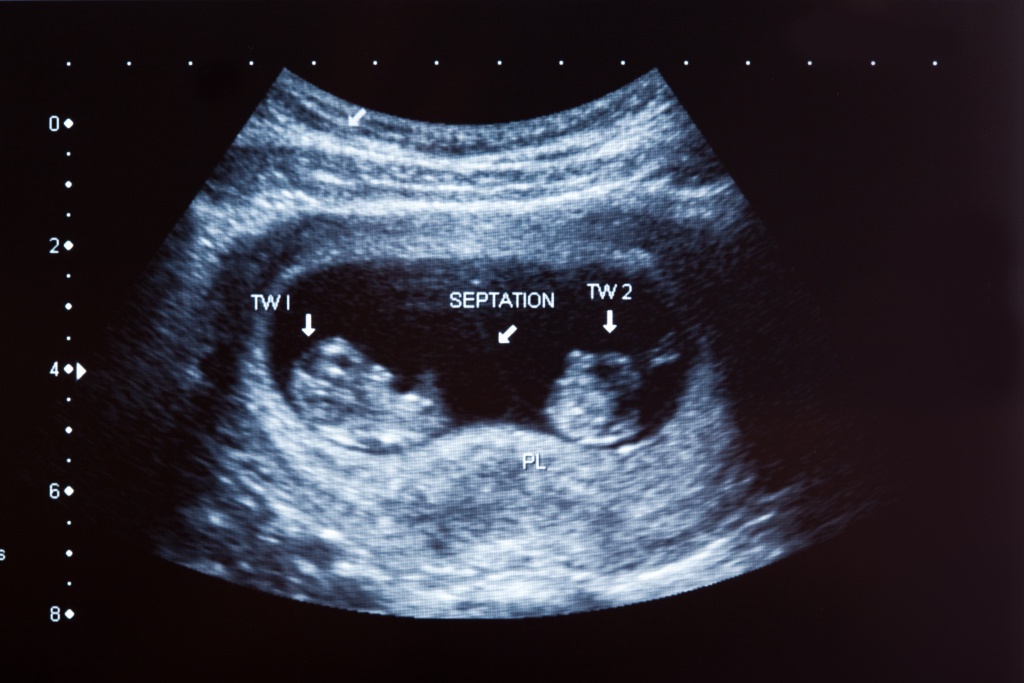

- определение количества плодов; оценка состояния ребенка – рост, вес, соответствие развития.

Первое исследование проводится для того, чтобы удостовериться, что беременность наступила. Также оно необходимо для выявления патологий матки и яичников. Позволяет оно также определить, нормально ли развивается плод, провести оценку его размеров.

Второе УЗИ дает возможность узнать пол малыша. Оно также показывает динамику его развития. Врач смотрит, нормально ли функционируют внутренние органы женщины.

Ультразвуковое исследование на 30й неделе – обязательное мероприятие, которое показывает наличие или отсутствие аномалий в развитии плода. Также это контрольный срок для отслеживания состояния ребенка в утробе матери. На этом этапе можно оценить положение ребенка и принять решение о вероятности проведения кесарева сечения.